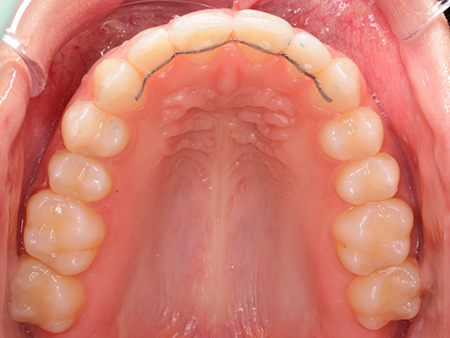

Aunque Ana no tenía un problema grave de mordida, acudió a Ferrus & Bratos para mejorar su estética dental. Sus dos incisivos -superior e inferior- no estaban en la posición adecuada y notaba cómo se iban desplazando, afectando a su sonrisa. Ana se puso en manos de la doctora Patricia Bratos, quien le recomendó un tratamiento con Invisalign para corregir su dentadura sin que ello afectara a su apariencia.

Después de extraer sus dos cordales superiores para conseguir mayor espacio en la boca, Ana comenzó su tratamiento, que tuvo una duración de 19 meses. Nuestra paciente asegura que los efectos han sido muy positivos y enseguida se acostumbró a llevar las férulas transparentes. Una vez finalizado su tratamiento, Ana observa cómo la expresión de su cara ha cambiado a mejor, pues sus dientes estás completamente alineados.